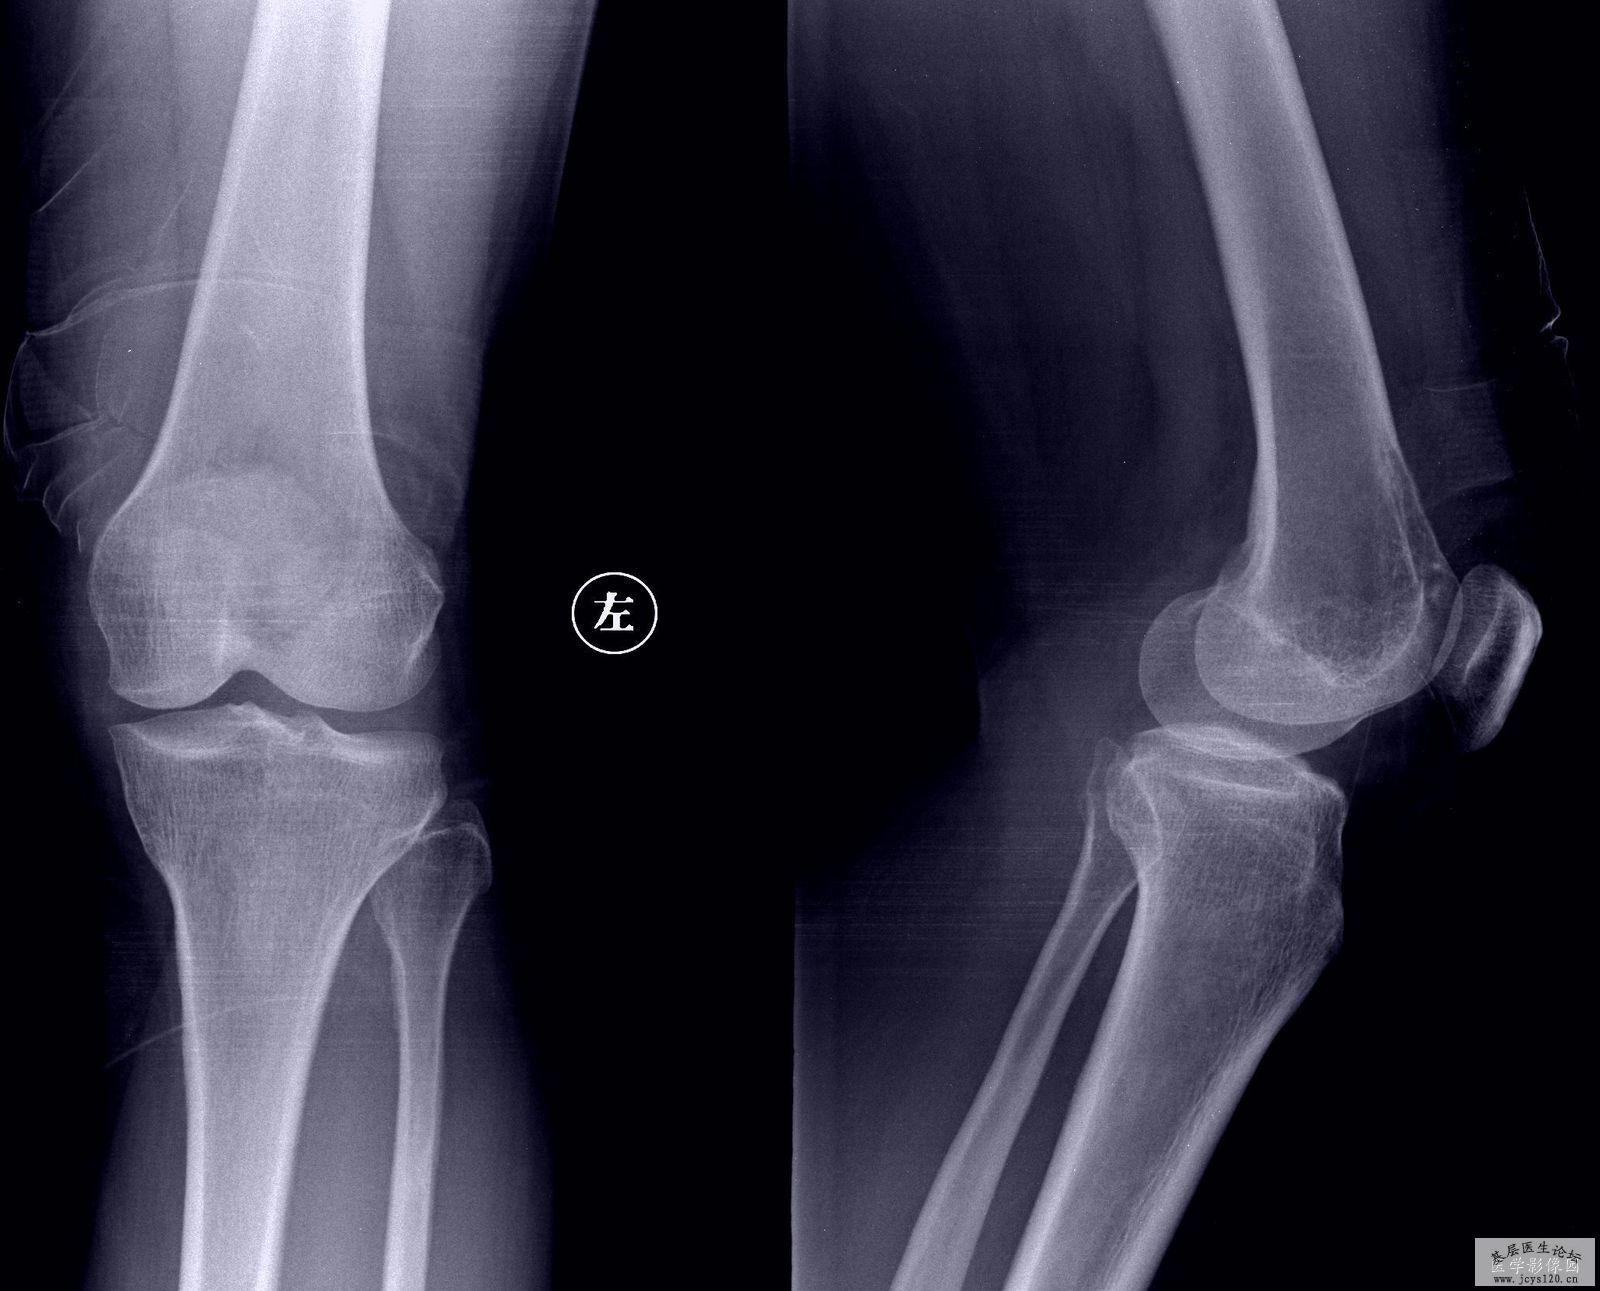

女,51岁,于50天前左膝部隐疼来诊,当时漏诊,病人回家未正规治疗。1月24日,病人疼痛减轻,股骨远端可见大面积骨质破坏区,前缘可见骨膜反应,软组织无明显肿胀。[/attachimg]请高手解答,多看片子有好处的。 阅读全文>